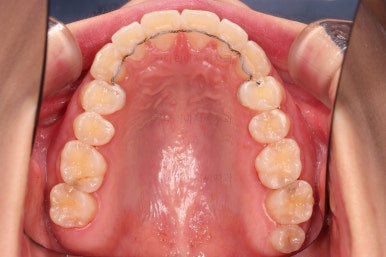

다시 틀어지지 말라고, 철사형 유지장치를 부착했고요.

과개교합이 재발되지 말라고 특수한 형태의 유지장치를 추가로 만들어드렸습니다.

부산앞니부분교정 전후 비교해 볼게요.

배열, 과개교합, 튀어나온 앞니, 심지어 약간의 입매개선까지.

난이도 높은 부분교정이 잘 마무리 되었습니다.